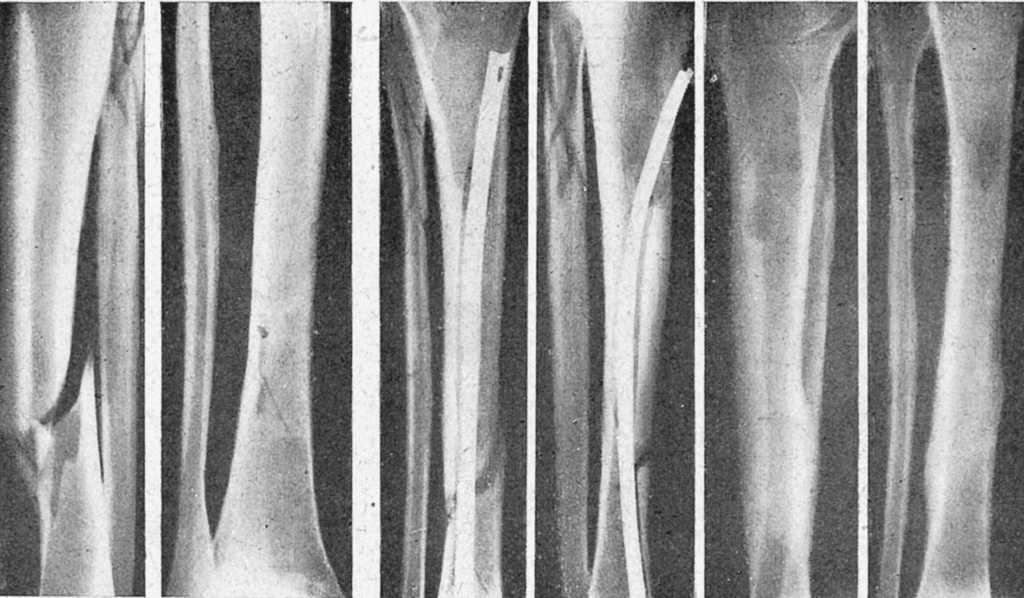

Figura 6. Fractura espiroidea tibia y conminuta peroné, que ni la extensión continua mantenía reducida. Enclavijamiento cerrado de la misma. La misma, consolidada.

Figura 7. Fractura de clavícula con gran desviación, en la que el enclavijamiento a cielo abierto consigue inmejorables resultados.

Figura 8. Fractura consolidada con desviación fragmentaria; osteotomía y enclavijamiento atípico; corrección de la desviación.